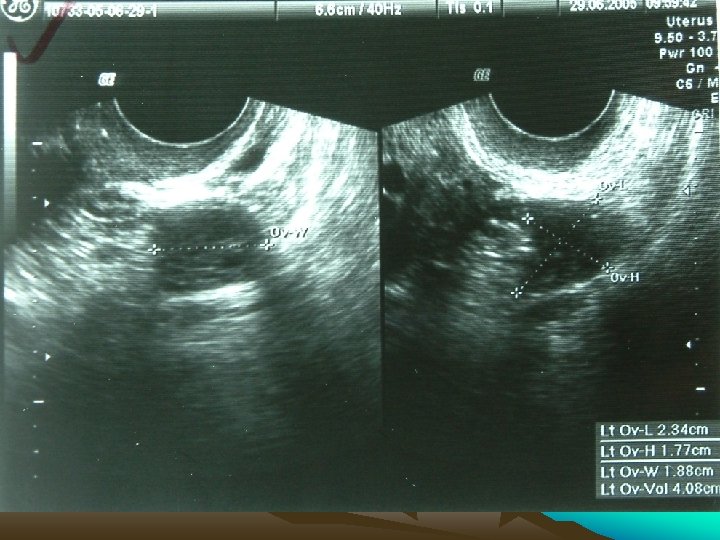

H: • 59 y , Postmenopausal, Dysphagia, & bleeding p/v, (year 2005 at AIIMS) • ANA +, Arthritis, Malar pigmentation • Ca ® Breast p. T 2 N 0 M 0 (July ‘ 02) • BCS • Breast RT + electron boost • Adjuvant CMF 6# • ER, PR & HER 2 -neu + • Tamoxifen 20 mg OD 2

Investigations • • • Chest X Ray USG CECT EUS Ba Swallow 3

Present Complaints • Bleeding P/V x 2 months (July 2005) • Hematemesis, Wt loss • GPE N

H: • • 59 y , Postmenopausal Ca ® Breast p. T 2 N 0 M 0 (July ‘ 02) BCS Breast RT + electron boost Adjuvant CMF 6# ER, PR & HER 2 -neu + Tamoxifen 20 mg OD

Bleeding PV • All causes + • Tamoxifen induced hyperplasia, polyp, carcinoma, • Mets from Metastatic Lobular breast CA